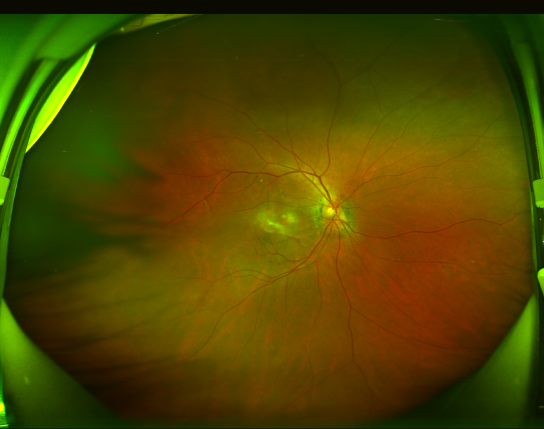

患者张阿姨(化名)自今年2月起发现右眼视物变形、中央视野出现暗影,经昆明艾维眼科医院眼底病科何雨檀主任接诊检查,确诊为渗出型老年性黄斑变性。通过光学相干断层扫描(OCT)显示黄斑区存在明显新生血管及出血病灶,荧光素眼底血管造影(FFA)进一步明确病变范围。何主任团队为其制定个性化抗VEGF药物治疗方案,配合光动力疗法(PDT),经过3次玻璃体腔注药治疗后,患者视网膜下积液吸收,最佳矫正视力显著改善。

患者治疗前的眼底照相和OCT检查